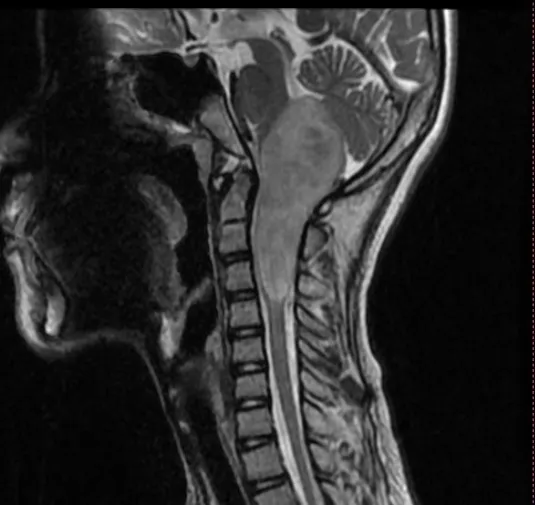

脑干肿瘤在成年患者中并不常见。出现的平均年龄是生命的四个十年,总生存期约为54-64个月。它们在流行病学数据中占全部脑肿瘤的小于2%。那些仅位于延...

延颈髓作为人体的呼吸循环中枢所在地,过去对于延颈髓肿瘤特别是髓内胶质瘤的处理存在较大风险,死亡率较高,但随着现代显微神经外科技术的发展,对于延...

延髓胶质瘤属于脑干胶质瘤的异质组。这些肿瘤起源于髓质,并可延伸至邻近结构,如脑桥、小脑下梗、小脑和脊髓上部。脑胶质瘤发生在儿童和成人患者...

延髓胶质瘤是绝症吗?脑干肿瘤在成人患者中很少见。出现的中位年龄为生命的四个十年,总生存期约为54-64个月。它们占流行病学数据中全部脑肿瘤的2...